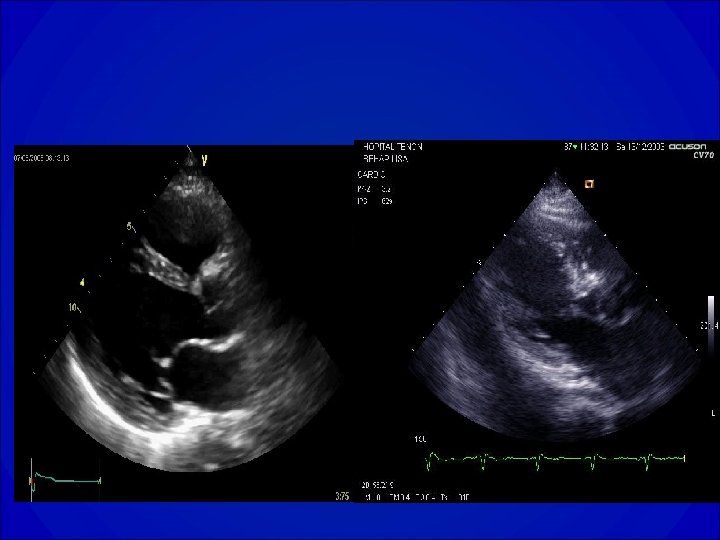

ECHOCARDIOGRAPHIE • Orientation étiologique et bilan de sévérité de la maladie • Evaluation de la fonction VG globale (dilatation ? Hypertrophie ? Fraction de raccourcissement, fraction d’éjection), cinétique segmentaire • Recherche d’une valvulopathie et évaluation de sa sévérité • Evaluation de la PAPS

Estimation des diamètres VG

VG normal Dysfonction VG